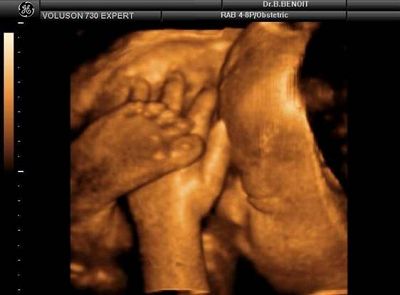

孕26~30周,是孕妇做四维彩超的最佳时间段。如果早于26周的话,胎儿的脂肪还非常少,通过四维彩超,甚至能看到宝宝的骨骼,不利于准确知晓胎儿是否健康发育。而晚于30周的话,宝宝已经下落到骨盆,这时通过四维彩超难以观察到胎儿的全身。

四维彩超都检查些什么呢?

1、首先四维彩超主要检查 面部畸形:四维彩超检查时重点观察胎儿双眼与眼眶是否等大、等圆,以及眼距测量,硬腭、软腭及上唇弧型曲线是否连续中断等。接下来筛查胎宝宝的颈部,看是否有异常包块。

2、脊柱畸形的筛查是要重点观察脊柱有无隆起,光带有无中断,排列有无紊乱,骶尾部有无肿块等。其他如腹部畸形、肢体畸形等通过逐一观察也不难发觉。

3、其次四维彩超主要检查 神经系统:无脑儿、脑积水、小头畸形、脊柱裂及脑脊膜膨出。在四维彩超胎儿筛畸检查中,首先要筛查的是头颅畸形。

4、检查中,检查者会严谨地观察胎头形态、脑组织(丘脑、小脑、小脑蚓部、颅后窝池、侧脑室)以及中线距两侧颅骨板的距离等,筛查无脑儿、露脑、脑积水等情况。

5、还有四维彩超主要检查 尿系统、肾积水、多囊肾及巨膀胱、尿道梗阻。

6、最主要的是四维彩超主要检查 消化系统:脐部肠膨出、内脏翻出、肠道闭锁及巨结肠等。短肢畸形、联体畸形、先天性心脏病及畸胎病等。